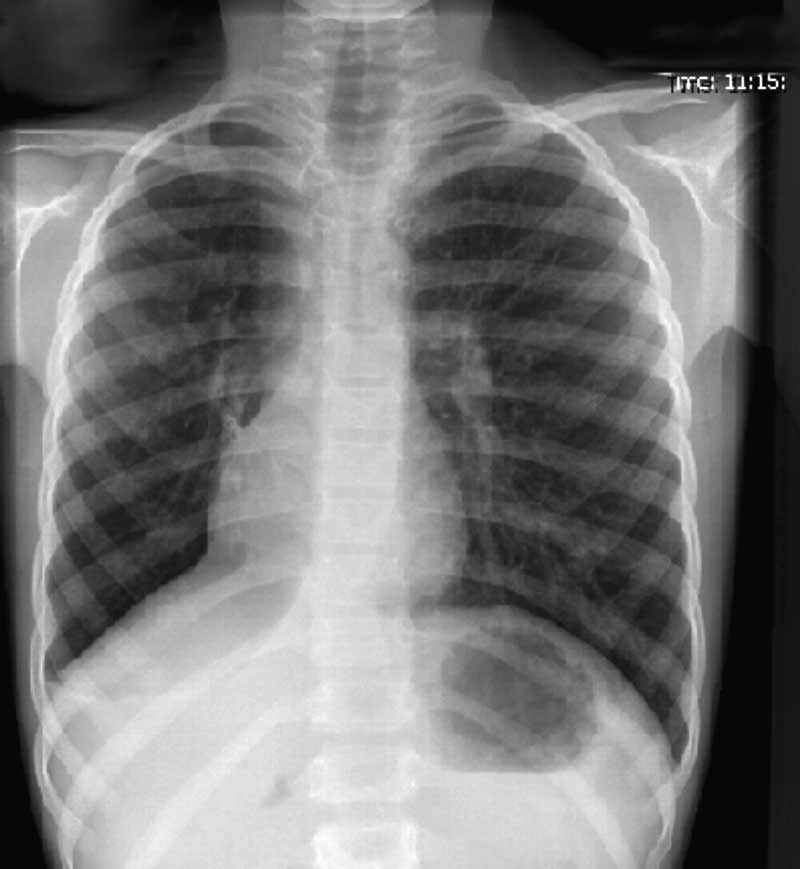

In addition a chest x-ray was ordered. PRESENTED BELOW.

ENLARGE X-ray left, X-ray right.

DO YOU HAVE AN INTERPRETATION OF THE CHEST X-RAY?